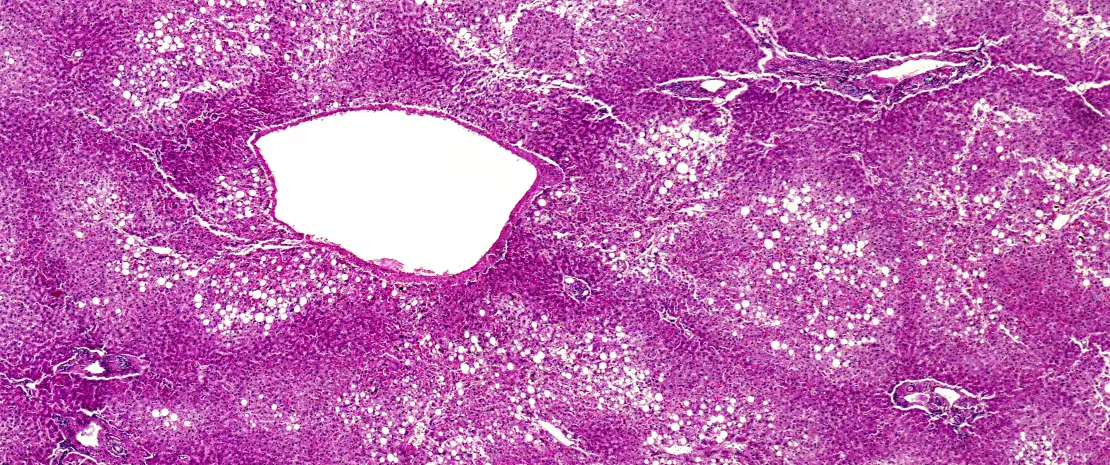

La stéatose hépatique non alcoolique (non-alcoholic fatty liver disease, NAFLD) est la maladie hépatique la plus fréquente dans les pays occidentaux et touche 25 à 30 % de la population générale. La NAFLD est une simple stéatose hépatique sans inflammation ou avec une inflammation minime. Elle peut s’aggraver en stéato-hépa- tite (NASH), laquelle est caractérisée par une stéatose, une inflammation et une fibrose. La NASH peut conduire à une cirrhose, qui est un facteur de risque de carcinome hépatocellulaire (CHC). La NAFLD associe obésité et insulinorésistance, deux symptômes qui caractérisent le syndrome métabolique.